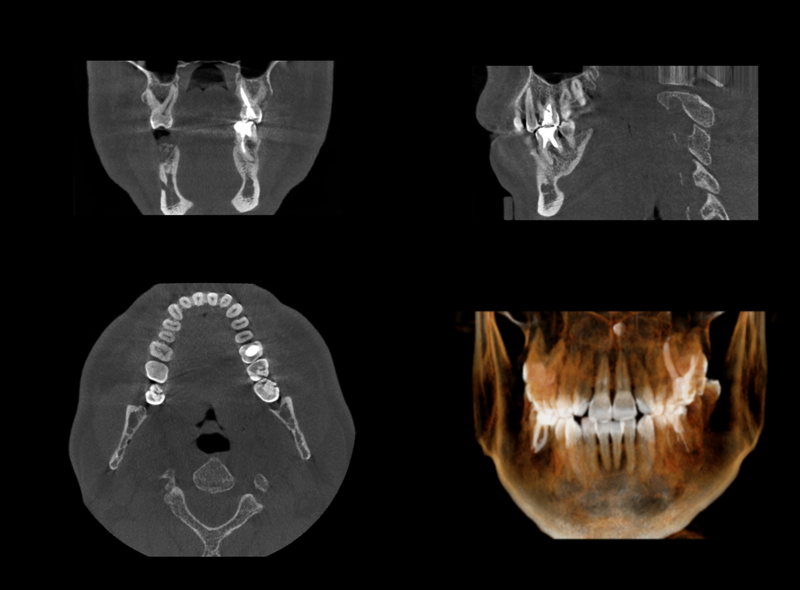

POINT歯科用CTを使用した精密診断

マイクロスコープで歯の中の細菌状況を確認しますが、CT撮影でさらに歯の内部を立体的・多角的にチェックできます。マイクロスコープでは見えない部分やレントゲンでは確認できなかった歯の水平的な断面図は根管治療に有用な情報が詰まっています。

マイクロスコープ、歯科用CTの両方を使用することによって複雑な根管を治療でき、今までは確認できなかった感染源に対してもアプローチできるため、根管治療がより確実で効果的なものになります。